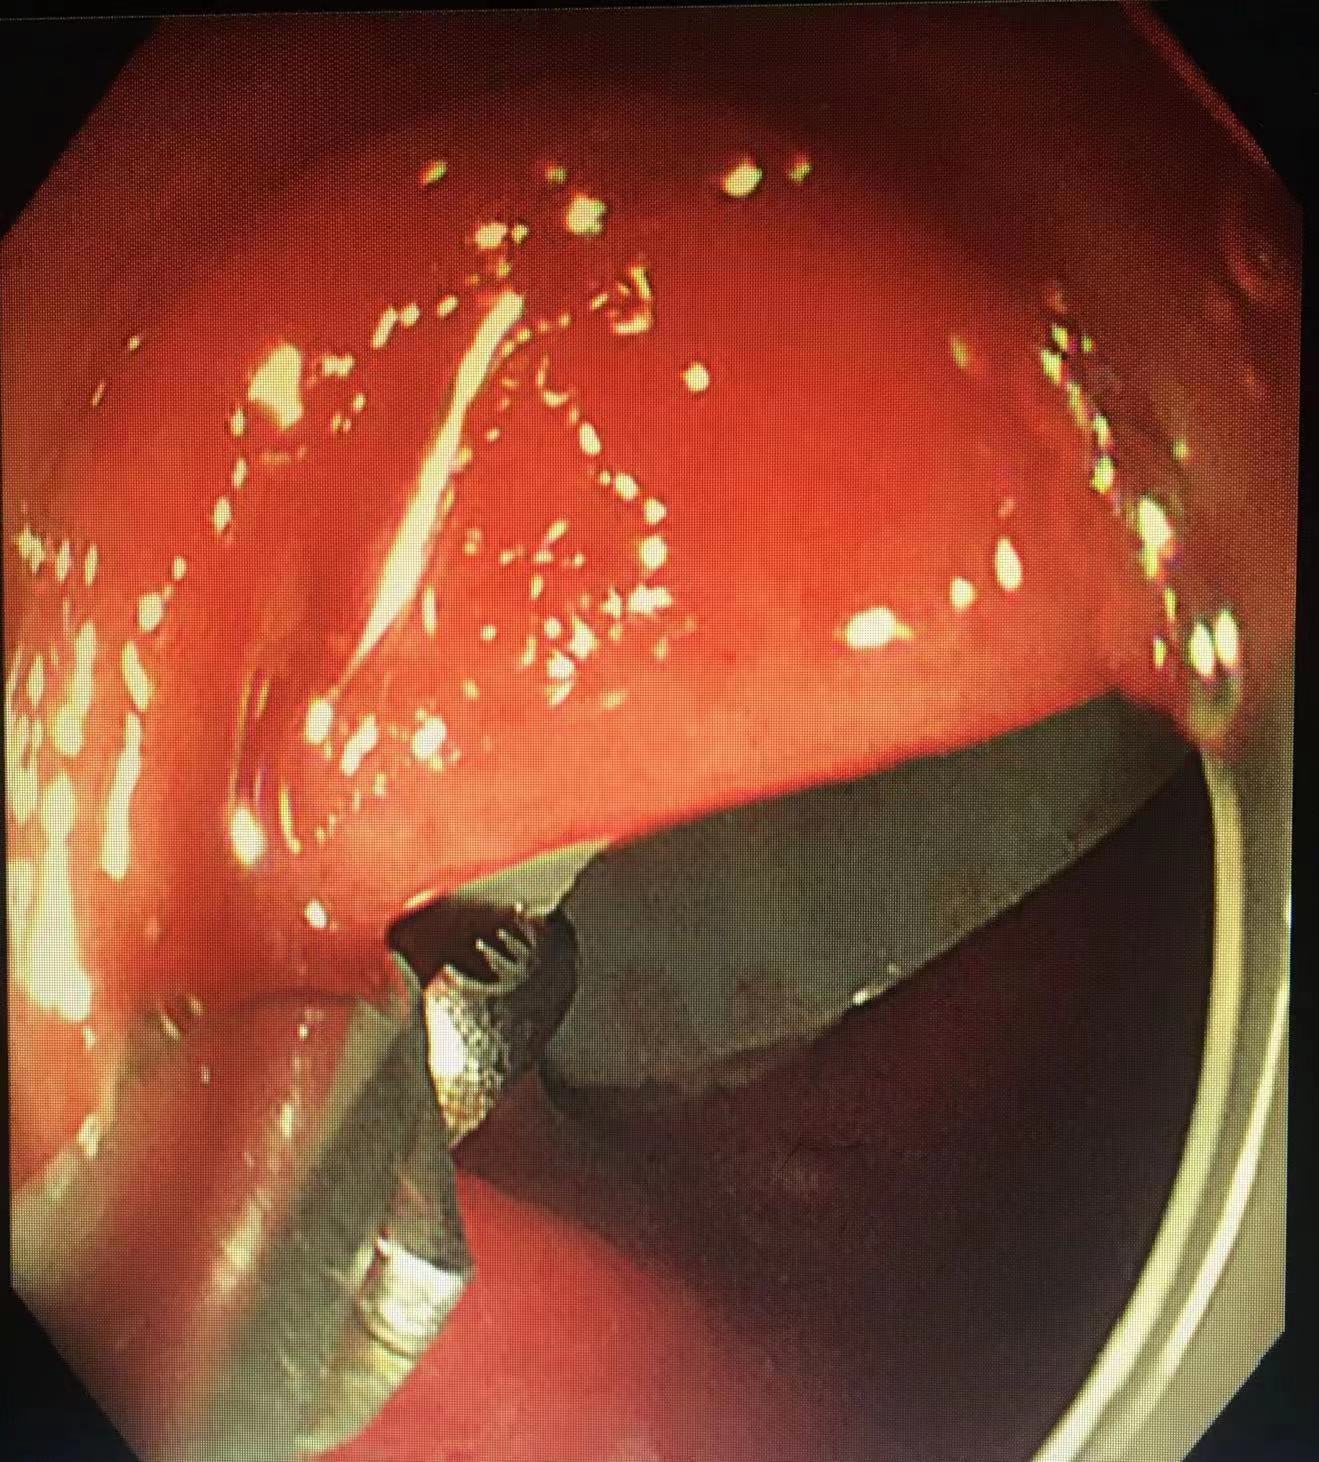

手术开始,通过肠镜观察到,一管状异物被紧紧地嵌顿在患者直肠乙状转弯处。由于患者曾多次尝试自行取出异物,导致直肠高度水肿,犹如一个橡皮套将异物包裹得十分紧实,还伴有溃疡出血,异物的一头仅隐约可见,很难找到有效的着力点移动异物,内镜下操作困难重重。

吕培华医生尝试使用圈套器、异物钳、鳄嘴钳等多种器械设备,反复不断地调整着角度、方向,在狭小的肠道空间中艰难地让异物沿着生理曲度挪移。每一分每一秒,都透着紧张与专注。在她的全神贯注与不懈努力下,异物一点点往肛门口移动。